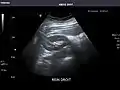

Right kidney

Kidneys: Right and left kidneys measure 11.5 cm and 12 cm in length respectively. No hydronephrosis. Small left lower pole kidney cyst.